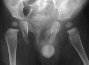

- Post Operative Day 18: R hip Xray: subluxation of R hip, possible metaphyseal

lucency consistent with osteomyelitis. Taken to OR for repeat I & D

of R hip via posterior approach with Penrose drains and hip spica cast

(15cc seropurulent fluid drained). Antibiotics changed to Oxacillin 225mg

IV q4.

Institute. Initial labs: WBC 15,100, ESR 72. R hip Xray: changes in proximal

. metaphysis including lucency and demineralization, hip subluxated. Treated

with oxacillin and Pavlik harness.

- 2 month Office Follow Up: Rt hip Xray: progressive destruction of capital

femoral epiphysis, cystic changes in metaphysis consistent with AVN.